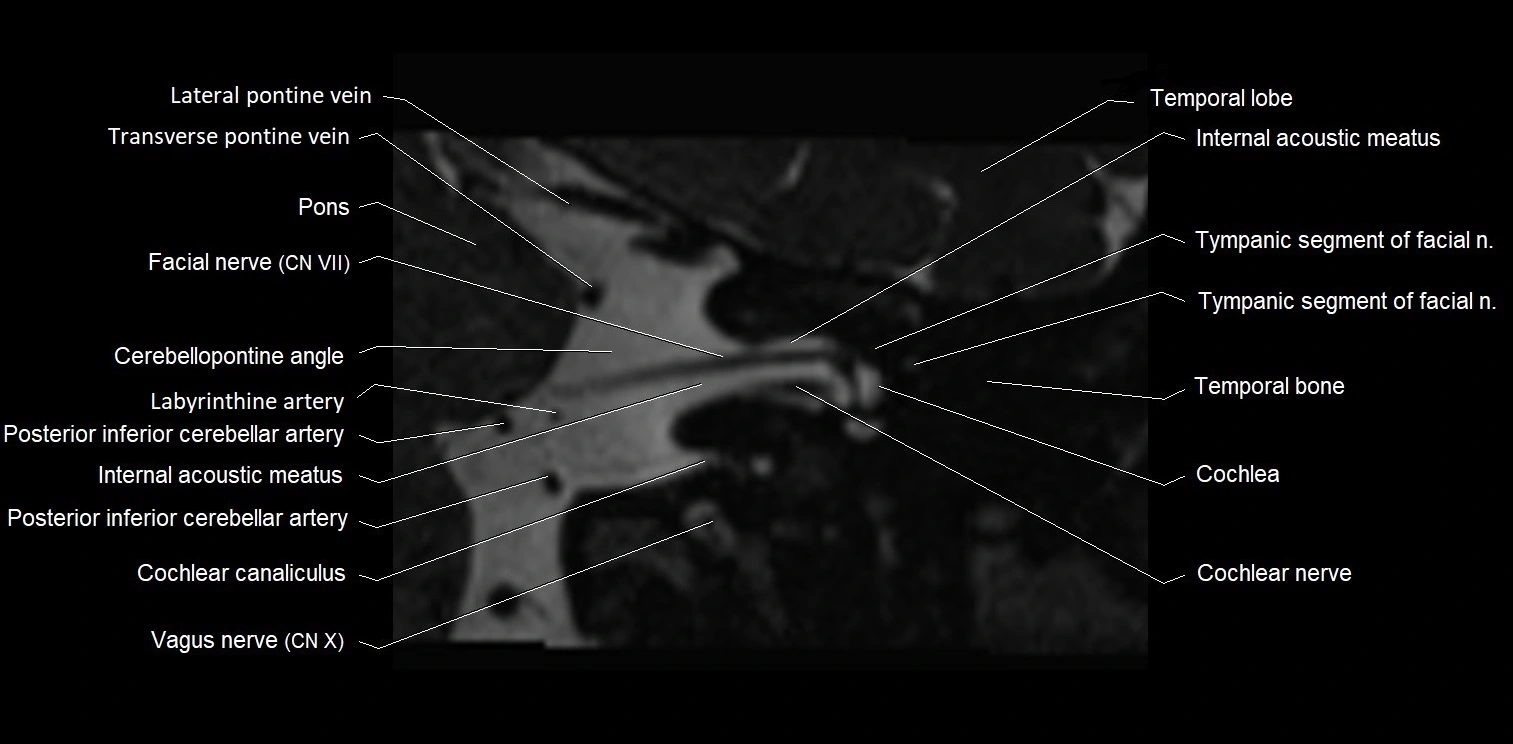

MRI images

image